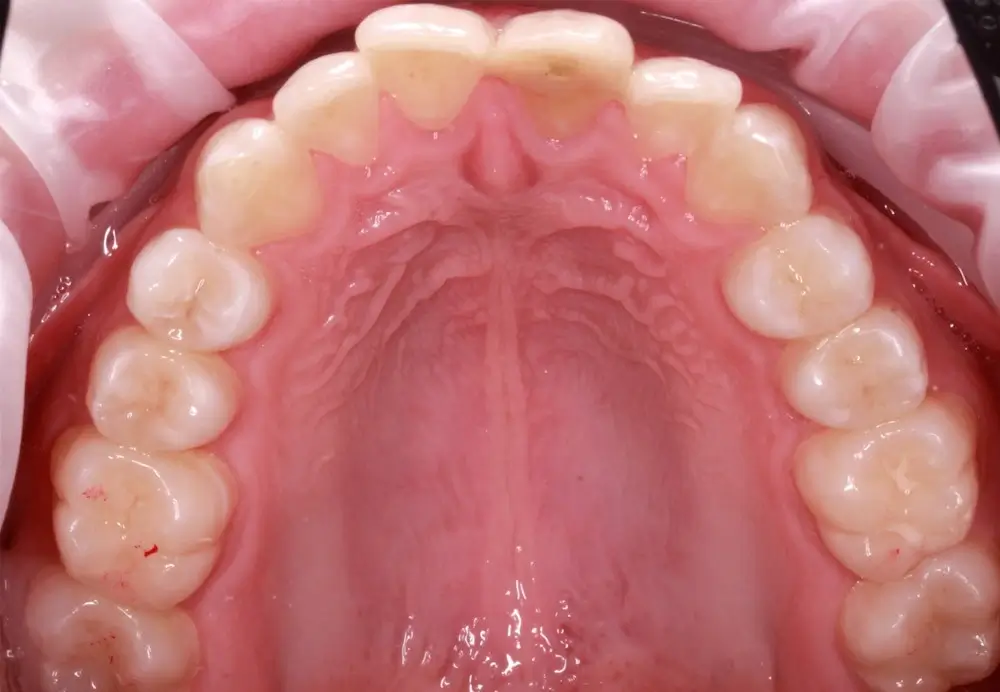

Кейс 9

Бирковская Екатерина Александровна

Количество кап ВЧ 23

Количество кап НЧ 23

ДО

ПОСЛЕ